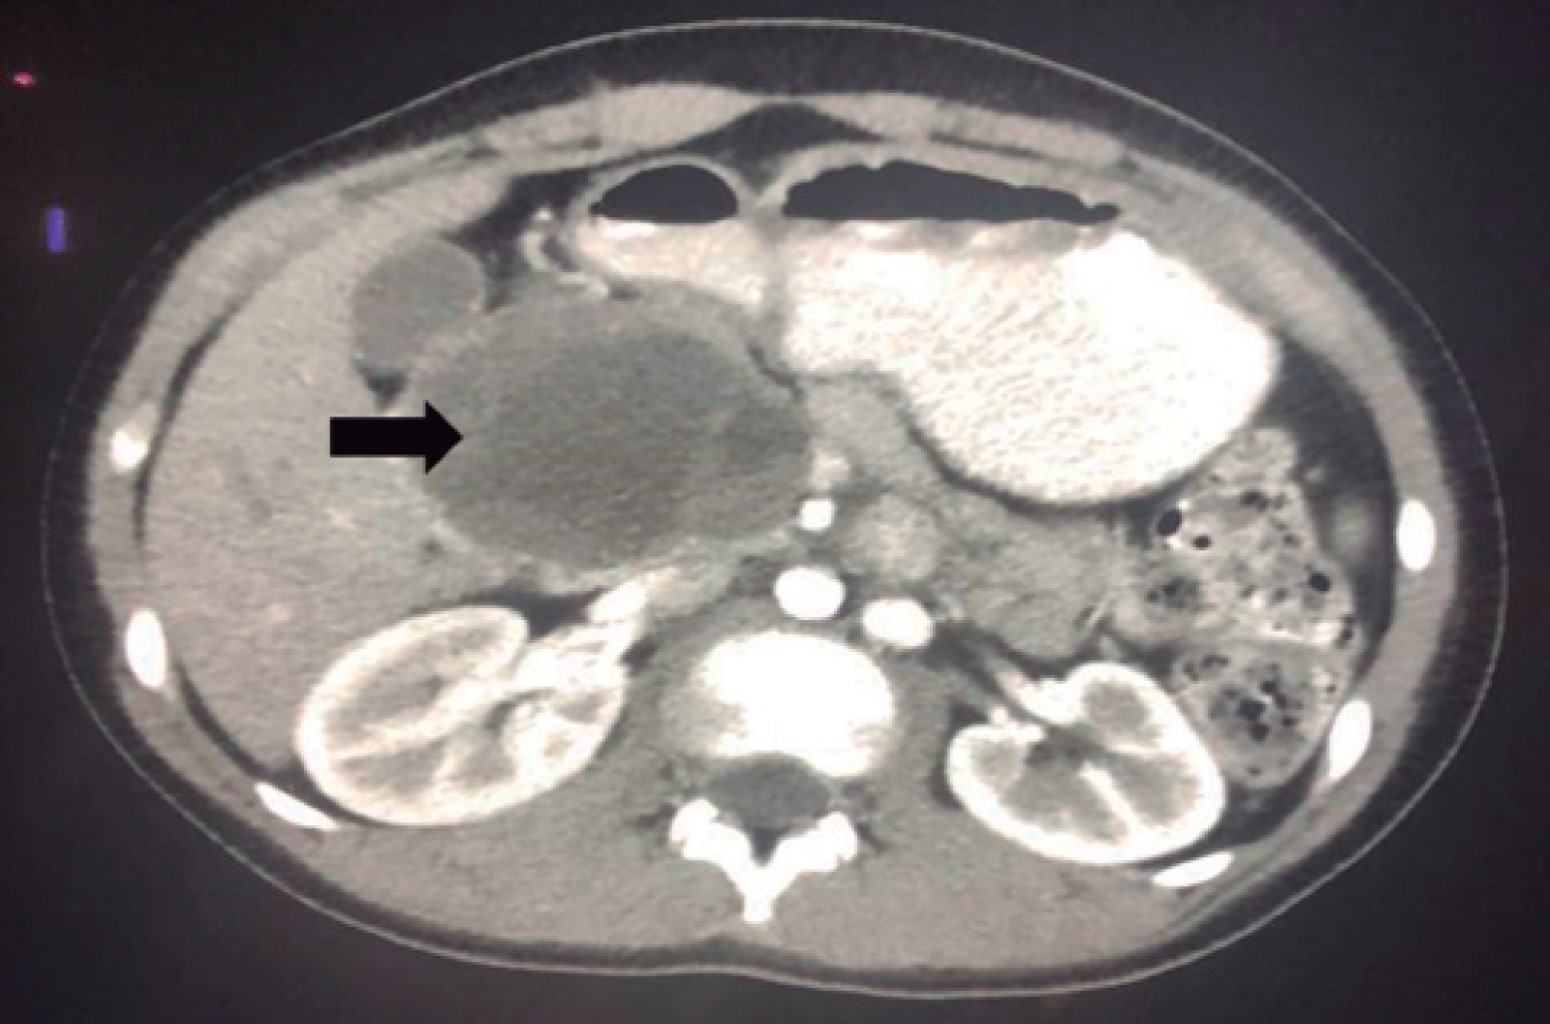

Imaging studies were performed including an abdominopelvic ultrasound study that showed a retroperitoneal heterogeneous tumor lesion with cystic areas in the vicinity of the head of the pancreas measuring 6 × 10.1 cm above the adrenal area. A computerized tomography (CT) scan of abdomen and pelvis simple and with intravenous contrast was performed showing evidence of a septate heterogeneous tumor lesion with contrast uptake in the periphery and septa, and presence of cystic areas of lower density located in the head of the pancreas of well-defined contours measuring 5. 9 × 6.7 × 7 cm. The pancreas body and tail were without alterations, and no dilatation of the duct of Wirsung, without presence of obliteration of the perivascular fat in the superior mesenteric artery or the spleno-portal axis, nor evidence of retroperitoneal adenomegaly were seen (Figure 1).